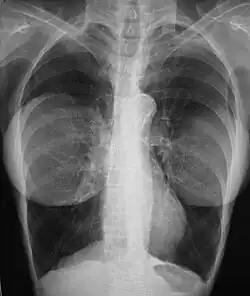

The presence of radiologically opaque breast implants (either saline or silicone) might interfere with the radiographic sensitivity of the mammograph, that is, the image might not show any tumor(s) present. In this case, an Eklund view mammogram is required to ascertain either the presence or the absence of a cancerous tumor, wherein the breast implant is manually displaced against the chest wall and the breast is pulled forward, so that the mammograph can visualize a greater volume of the internal tissues; nonetheless, approximately one-third of the breast tissue remains inadequately visualized, resulting in an increased incidence of mammograms with false-negative results.[118][119]

The breast cancer studies Cancer in the Augmented Breast: Diagnosis and Prognosis (1993) and Breast Cancer after Augmentation Mammoplasty (2001) of women with breast implant prostheses reported no significant differences in disease-stage at the time of the diagnosis of cancer; prognoses are similar in both groups of women, with augmented patients at a lower risk for subsequent cancer recurrence or death.[120][121] Conversely, the use of implants for breast reconstruction after breast cancer mastectomy appears to have no negative effect upon the incidence of cancer-related death.[122] That patients with breast implants are more often diagnosed with palpable—but not larger—tumors indicates that equal-sized tumors might be more readily palpated in augmented patients, which might compensate for the impaired mammogram images.[123] The ready palpability of the breast-cancer tumor(s) is consequent to breast tissue thinning by compression, innately in smaller breasts a priori (because they have lesser tissue volumes), and that the implant serves as a radio-opaque base against which a cancerous tumor can be differentiated.[124]

The breast implant has no clinical bearing upon lumpectomy breast-conservation surgery for women who developed breast cancer after the implantation procedure, nor does the breast implant interfere with external beam radiation treatments (XRT); moreover, the post-treatment incidence of breast-tissue fibrosis is common, and thus a consequent increased rate of capsular contracture.[125] There is tentative evidence that women who have had breast augmentation, have worse breast cancer prognosis.[126] The use of implants for breast reconstruction after breast cancer mastectomy appears to have no negative effect upon cancer-related death.[122][127]

There have been multiple reported cases of other adverse effects of mammography of women with breast implants; ruptures resulting from pressure exerted on the breast implant make up a majority of these cases.[128] Compression may also lead to pain or exacerbate already existing pain in the breasts.[128]